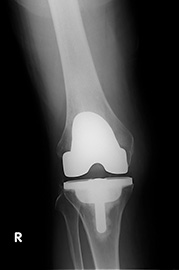

写真1は人工膝関節置換術前、写真2は 同じ方の術後のX線写真です。手術前は外出も避けるほどの痛みがあり、閉じこもりがちな日々をおくられていました。手術前は膝の軟骨が摩り減り、ふともも の骨と、すねの骨がお互いに擦れ合うような状態になっています。この患者さんは、手術と術後のリハビリテーションをがんばり、現在は買い物や旅行なども楽 しめるようになって、表情も非常に明るくなられました。

| 【写真2】術後 | 【写真1】術前 |